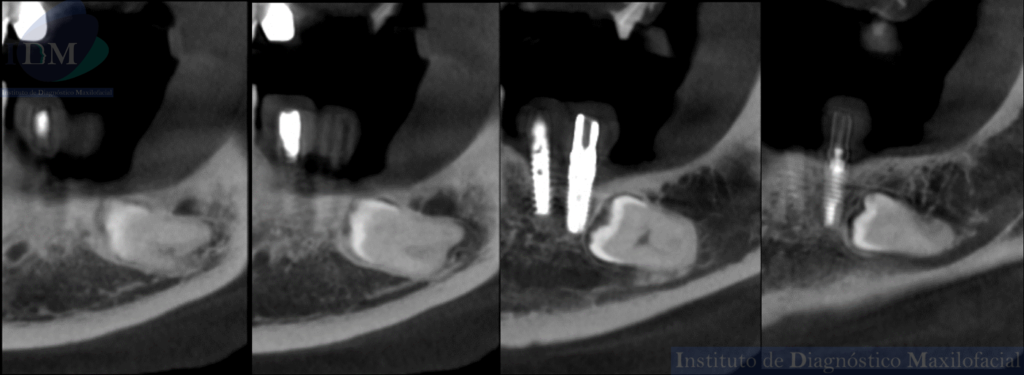

CORTES TANGENCIALES

Siendo así que en la tomografía volumétrica de haz cónico se evidencia una hipercementosis radicular, con los segmentos radiculares contactando con el conducto dentario inferior. Finalmente se evidencia un borramiento del espacio del ligamento periodontal compatible con anquilosis dentaria.

A la evaluación de la radiografía panorámica se evidencia reabsorción ósea alveolar bimaxilar, edéntulo parcial bimaxilar y presencia de múltiples implantes con prótesis sobre implantes así como tratamientos restaurativos. Siendo lo más destacado una molar retenida en cuerpo mandibular izquierdo, la cual esta mesioangulada.